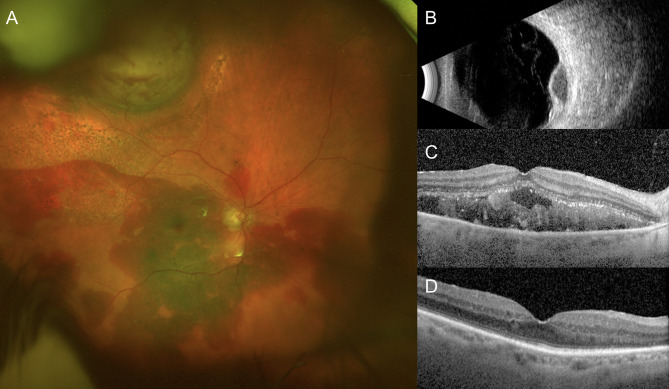

Purpose: To evaluate the clinical characteristics and treatment outcomes of breakthrough vitreous hemorrhage secondary to peripheral exudative hemorrhagic chorioretinopathy (PEHCR).

Methods: This retrospective study included 14 eyes from 14 patients with vitreous hemorrhage secondary to peripheral retinochoroidal mass lesions. Data collected included demographic profiles, clinical presentation, multimodal imaging findings, and treatment outcomes following pars plana vitrectomy (PPV), intravitreal anti-VEGF injections, or laser photocoagulation.

Results: The median age at presentation was 83 years (range, 58-91), with nine females (64.3%). Median presenting visual acuity (VA) was 1.3 logMAR (range, 0.3-2.7). All patients had normal intraocular pressure. Bilateral PEHCR was observed in 50%, though hemorrhage occurred unilaterally. Unifocal lesions were present in 71.4%, with a mean lesion thickness of 3.4 mm (range, 1.5-6.8 mm). Dense vitreous hemorrhage obscuring posterior pole details was seen in eight eyes (57.1%) and required PPV. The remaining six eyes, with moderate hemorrhage, improved spontaneously without surgery. Intravitreal anti-VEGF therapy was administered in five eyes for macular involvement or to prevent recurrent hemorrhage. At a median follow-up of 11.7 months (range, 3-63), median VA improved to 0.36 logMAR (range, 0.1-2.0). The mean VA gain was 0.76 logMAR in the vitrectomy group (p = 0.004) and 0.55 logMAR in eyes without macular involvement (p = 0.024). However, five eyes (35.7%) had final VA ≤ 20/200 due to macular pathology consistent with age-related macular degeneration or polypoidal choroidal vasculopathy-like changes.

Conclusion: PEHCR with breakthrough vitreous hemorrhage is a rare but important diagnostic consideration in patients presenting with peripheral retinochoroidal mass-like lesions. PPV and intravitreal anti-VEGF therapy may improve visual outcomes in these cases. However, visual recovery may be limited in cases with macular involvement due to irreversible retinal damage. Early diagnosis and tailored management are essential to optimize outcomes and avoid misdiagnosis.